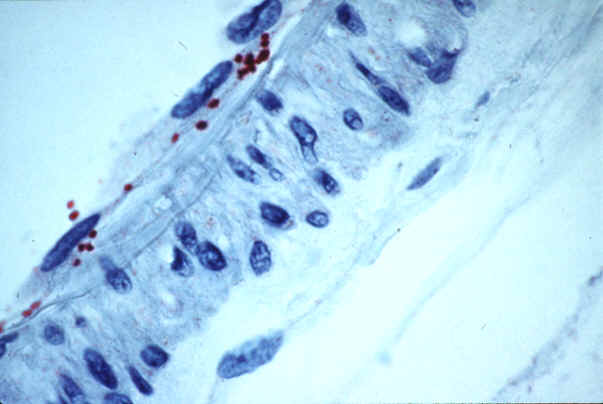

Rickettsia rickettsii

(ROCKY MOUNTAIN SPOTTED FEVER)

Photo courtesy of the CDC - http://www.cdc.gov/ncidod/dvrd/rmsf/index.htm

Rickettsia rickettsii is a species of small bacterium that are the causal agents of the infection known as Rocky Mountain Spotted Fever. These obligate intracellular bacteria have cell walls, lack flagella, are gram-negative, perform aerobic respiration, and multiply through binary fission in the nucleus or the cytoplasm of their host cells. Once inside they have multiplied, they often will damage and kill a large number of cells by causing blood to leak through tiny holes in blood vessel walls into adjacent tissues. They occur either singly, in pairs, or in strands. They range in size from 0.2 by 0.3 um to 0.5 by 2.0 um. (Emerging Infection Diseases, 1998) They are difficult to see in tissues using routine histologic stains and often require special staining methods. (CDC, 2005) They have diplococcoid bodies and are maintained in nature by through the transstadial and transovarial passage beween different tick vectors. (Wattam, 2004) They can infect, remain for extended periods of time, and multiply in numerous types of hosts, but most commonly infect mammals and arthropods in a relatively complex host-parasite interaction. (Emerging Infection Diseases, 1998)